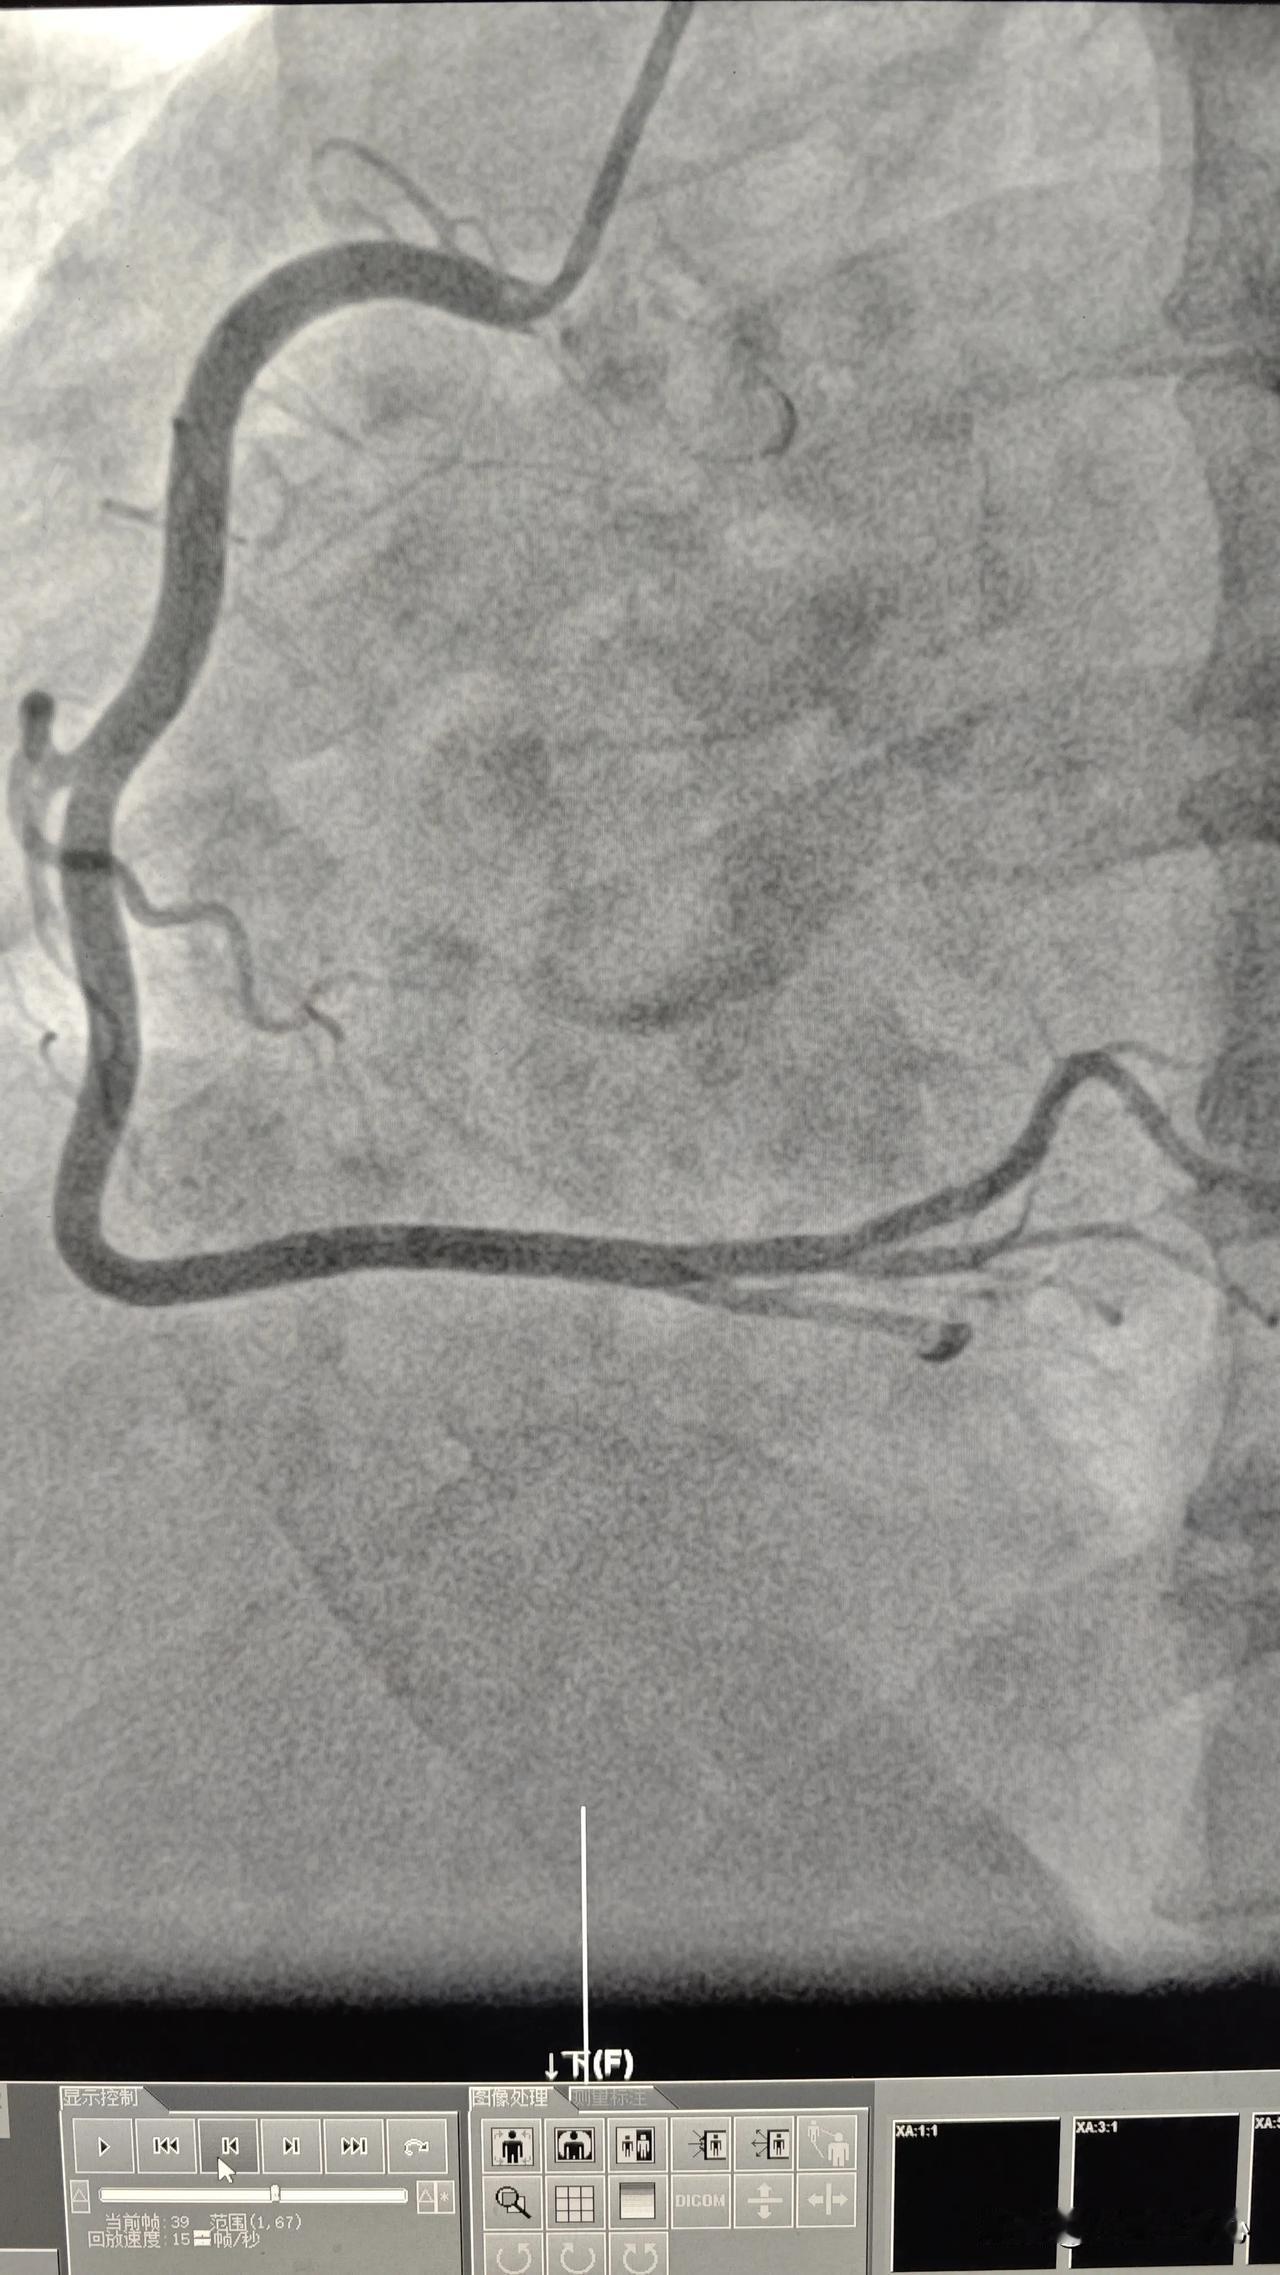

血管正常也会有心肌缺血症状。 47 岁男性患者,间断胸痛 2 年入院,活动量大的时候症状明显,平常有吸烟饮酒的情况。也看过很多冠心病心梗的新闻,非常害怕。担心自己也是冠心病,再加上人到中年,上有老下有小,自己是家里的顶梁柱,可不能出意外。多方咨询以后决定还是做一个心脏造影。 造影发现心脏血管只有轻微动脉硬化,尤其有右冠状动脉几乎没有任何动脉硬化(图一),但是为什么会有典型的活动以后胸闷呼吸困难这些心肌缺血的表现呢? 仔细观察患者的造影动态图像发现,患者冠状动脉内血流缓慢,对于一般患者来说,心脏跳动 1-2 次,血液可以从血管近端流到远端。而这个患者心脏跳动 4 次,血液才从近端流到远端。虽然没有明显的狭窄,血流量没有减少,但血流速度减慢,是另一种形式的心肌缺血。 引起这种情况的原因主要是血管内皮功能不好导致。治疗主要是以药物为主。还有需要戒烟,减少对血管功能的影响。此外,适当多运动,增强体质。